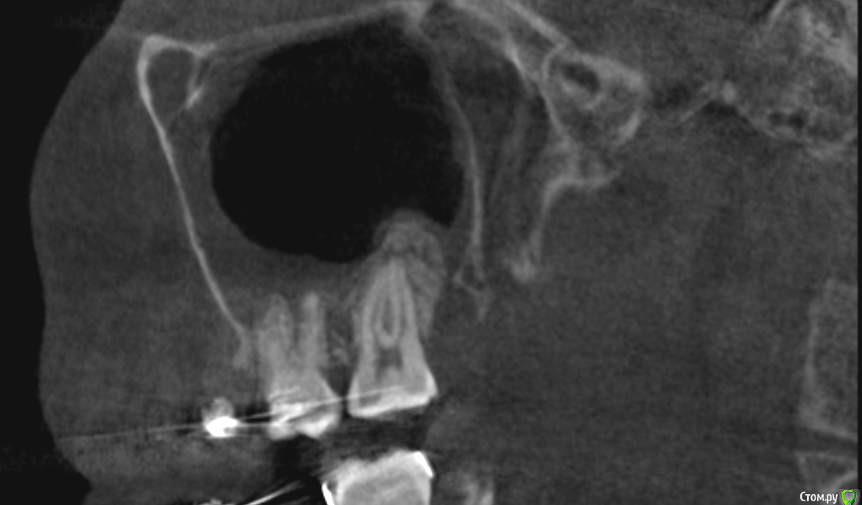

It'sGeorgy Опубликовано 30 ноября, 2019 Поделиться Опубликовано 30 ноября, 2019 Всем доброго времени суток! Пациентке в сторонней клиники 1.5 года назад удаляли 2.8 зуб. Удаление заняло больше часа. После этого, с ее слов был гайморит, который пол года не могли вылечить т.к. не могли найти причину. На срезах(кт не могу прикрепить к сожалению сейчас):1 - Пазуха + сообщение2 - Состояние лунки3 - Недоудаленный корень в области 2.7 зуба(?) На слизистой ОАС не нашел. На данный момент активных жалоб нет, но порой "Побаливает". - Стоит ли лезть и пытаться закрывать сообщение? Какова методика операции и где можно про нее почитать?(До этого закрывал только ОАС с выходом на слизистую с помощью лоскута со щеки + ССТ) Или просто передать ЛОРу на удаление полипов из пазухи? - Стоит ли лезть и пытаться удалять корень или пусть там полежит? Ссылка на комментарий

It'sGeorgy Опубликовано 4 декабря, 2019 Автор Поделиться Опубликовано 4 декабря, 2019 тогда что Вы собрались закрывать???На КТ видно, что лунка не зарастает костной тканью из нее есть сообщение с пазухой. Прошло уже 1.5 года. Вопрос в том, нуждается ли это в лечении и где можно почитать про ведение таких случаев. Ссылка на комментарий

___49___ Опубликовано 4 декабря, 2019 Поделиться Опубликовано 4 декабря, 2019 (изменено) На КТ видно, что лунка не зарастает костной тканью из нее есть сообщение с пазухой. То , что костной ткани нет - видно. Не зарастает , но при этом нет ороонтрального сообщения - это как ? Если вы считаете, что наличие кости между полостью рта и пазухой обязательно , то это не так, недавно закрыл ороонтральное сообщение которому более 10 лет , при этом костный дефект(костное окно) между полостью рта и пазухой примерно 8 *8 мм. через 1.5 месяца ротоносовая проба отрицательна , пазуха чистая, костное окно без изменений и так скорее всего и останется , считаю пациентку выздоровевшей . В вашем случае наблюдал бы пациентку в динамике, показаний к травматичным операциям на данный момент нет , вероятность того, что апекс там проживет всю жизнь( так как полная ретенция вы писали и надеюсь без альвеолита ) и более не проявит себя, вполне имеет место быть . Изменено 4 декабря, 2019 пользователем ___49___ 2 Ссылка на комментарий